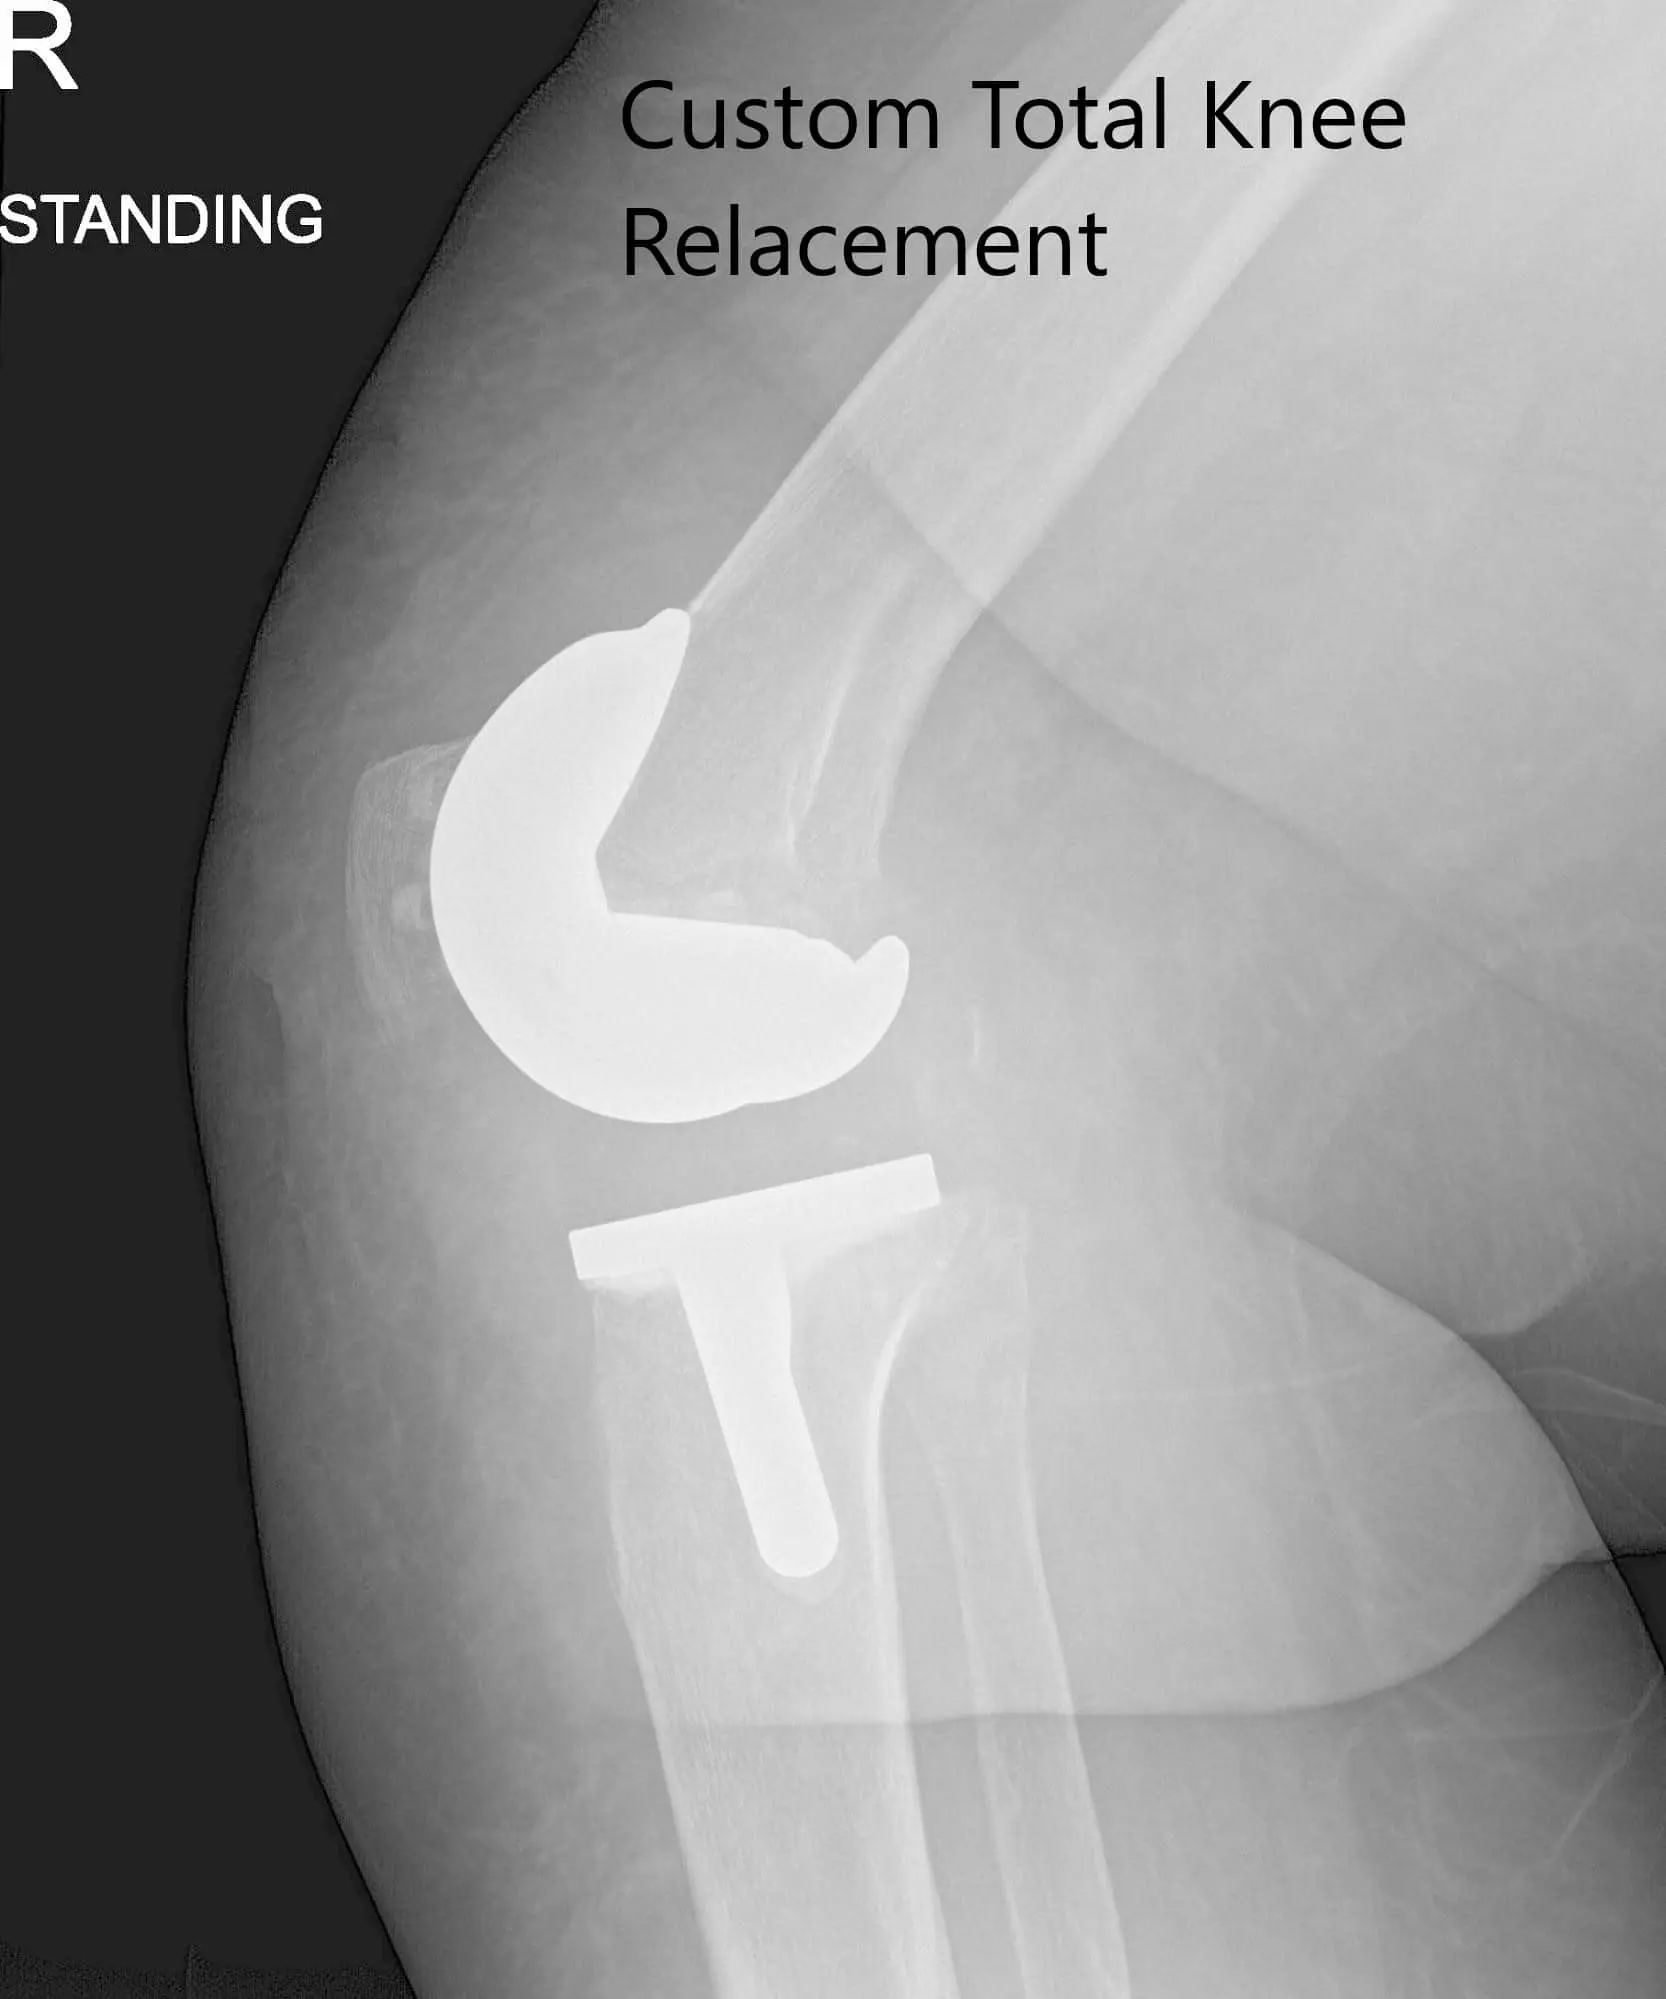

Postoperative x-ray images showing AP and lateral views of the right knee

Her postoperative x-ray demonstrated excellent alignment. Outpatient physical therapy was started for increasing the range of motion and strengthening of muscle. On a subsequent follow-up visit, she reported zero pain with a full range of motion. She was back to her baseline activities and expressed satisfaction at the outcome of the surgery. She follows up as needed.